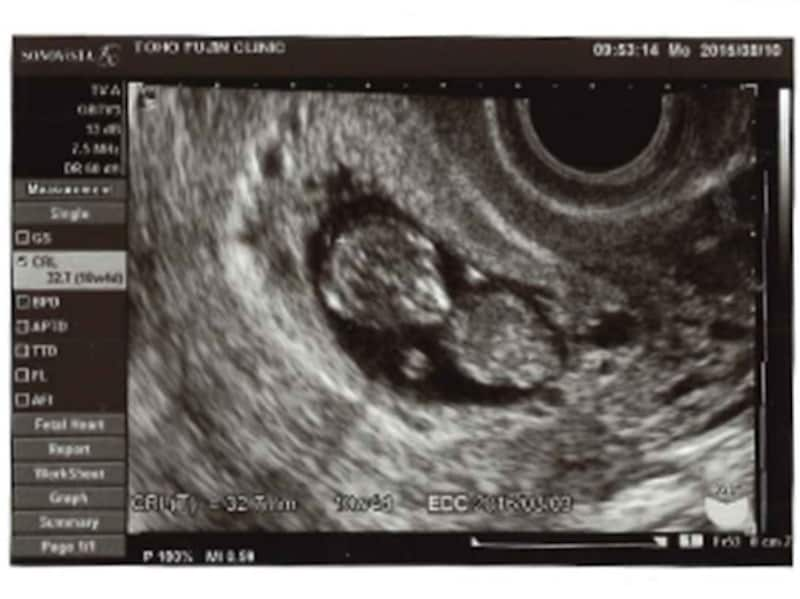

妊娠10週(10w)頃の赤ちゃんは2頭身で、これまでの丸まった姿勢から体はまっすぐになってきます。骨と筋肉が急成長し、骨はだんだん固くしっかりとしてきます。胴ものびてきて、体の形は、新生児に近くなってきています。超音波検査で見ても、赤ちゃんには丸い手足がついているのがわかります。手足をバタバタする様子を見せることもあります。

まぶたができてきて、赤ちゃんの目が閉じるようになってきました。耳も完成形になりつつあります。超音波検査でも、顔立ちがはっきりしてきて、あごもスッとして見えるでしょう。また、すでに20本の乳歯の芽が歯肉の中に形成されています。髪の毛のもともできてきます。皮膚は、少し厚みが出てきて、透明ではなくなってきました。